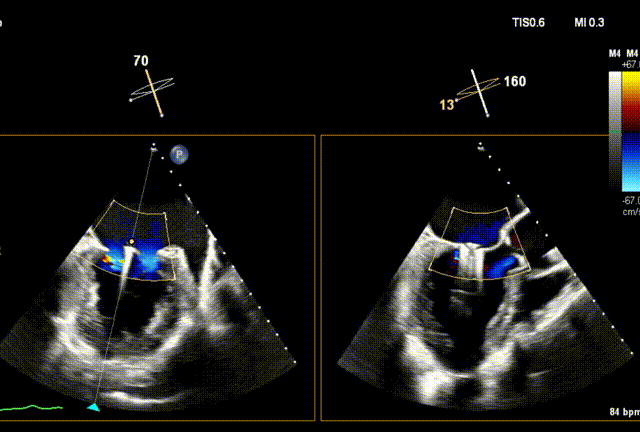

术后Xplane彩色图像

夹合后二尖瓣反流量0+,平均跨瓣压差3mmHg